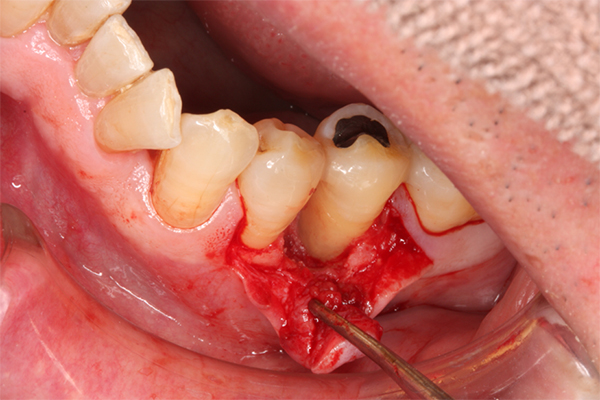

エムドゲインは、エナメルマトリックスという幼若豚の歯の組織から抽出したタンパク質です。これも歯周外科処置と同様に進め、歯石や感染物の除去を行い歯根面を徹底的に綺麗に清掃した後、リン酸などで歯根を処理し、歯根面へエムドゲインを塗布し縫って(縫合)処置を終わります。

*エムドゲインゲル溶液の塗布

*リグロスの塗布